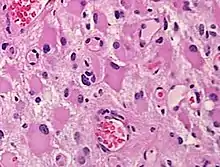

Histopathology of a gemistocytic astrocytoma. Neoplastic gemistocytes are angular shaped with abundant, glassy, eosinophilic cytoplasm and eccentric nuclei with distinct nucleoli.

When present in anoxic-ischemic brains, gemistocytes are regularly encountered in glial neoplasms, also known as glioma, which is a type of tumor that occurs in the brain and spinal cord. Usually, gliomas begin in the glial cells that surround the nerve cells to help them function. Many gliomas exhibit cells that do not exist in normal brain tissue and are not seen in glial differentiation.[1] Of these gliomas are astrocytomas, which is a type of cancer that occurs in the brain or spinal cord. The main role of astrocytes is to maintain brain homeostasis and neuronal metabolism. When the astrocytes become activated, they begin to respond to damage.[3] Astrocyte activation, known as astrogliosis, responds to neurological trauma, infections, degradations, epilepsy, and tumorigenesis. Each neurological insult plays a major role in astrocyte activation and response to that specific damage. In some astrocytomas, the number of gemistocytes is extremely overwhelming, terming it a “gemistocytic astrocytoma.” Not only are gemistocytic cells present in astrocytomas, but they are also found in various glial tumor cells; for example, oligodendrogliomas, mixed oligoastrocytomas, glioblastomas, and pleomorphic xanthoastrocytomas. Gemistocytes are known to have a large cytoplasmic mass, long, branching processes, and increased cytoplasmic filaments.[1] The cytoplasm of gemistocytes stains positive for glial fibrillary acidic protein, GFAP. While the intermediate filaments in gemistocytes are diffused throughout the cytoplasm, which indicates cellular disintegration. Within these different tumor types, the term “mini-germistocytes” is used for smaller gemistocytes, that are usually found in oligodendroglial tumors. Mini-germistocytes are found to have a very ordered arrangement of filaments throughout the cytoplasm, but may also transform into the end-state morphology of the larger gemsitocytic cells. Studies have suggested that both classic gemistocytes and mini-gemistocytes show similar genetic variation to non-gemistocytic tumor cells.[4] Mini-germistocytes, usually found in oligodendroglial tumor cells, express gliofibrillary oligodendrocytes, or GFOCs, which are capable of transforming the mini-gemistoctyes into larger gemistocytes.